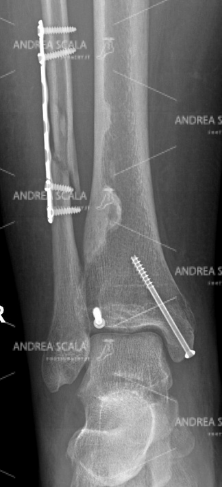

La RXgrafia anteriore della caviglia mostra la protesi della caviglia. 5 anni dopo la frattura, all’età di 39 anni, la paziente ha rifiutato l’artrodesi, cioè il blocco della caviglia e si è sottoposta all’intervento di protesi di caviglia. Si vede molto bene che la placca e le viti sul perone sono rimaste al loro posto indisturbate. Il perone non è stato toccato perché è un elemento anatomico che garantisce la stabilità della caviglia. Le componenti appaiono ben allineate all’asse della gamba.

La RXgrafia laterale della caviglia mostra la protesi della caviglia. Per quale motivo si sarebbe dovuto rompere nuovamente il perone? Perché avrebbe dovuto sacrificare una parte che era guarita? Perché avrebbe dovuto rompere di nuovo una parte che aveva impiegato tanto tempo a consolidare e a guarire? Per fare un favore a chi? Si nota che le componenti della protesi sono parallele al piano d’appoggio al suolo.